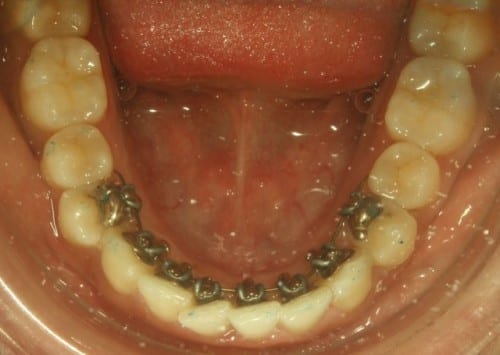

Le propusimos tratarse con ortodoncia lingual, solo de colmillo a colmillo, en la arcada inferior, con Incognito Lite (marca 3M), los brackets linguales con Incognito Lite son un tratamiento completamente invisible y económico que es la solución ideal para este tipo de problemas: brackets y ortodoncia hecha a medida para cada persona.